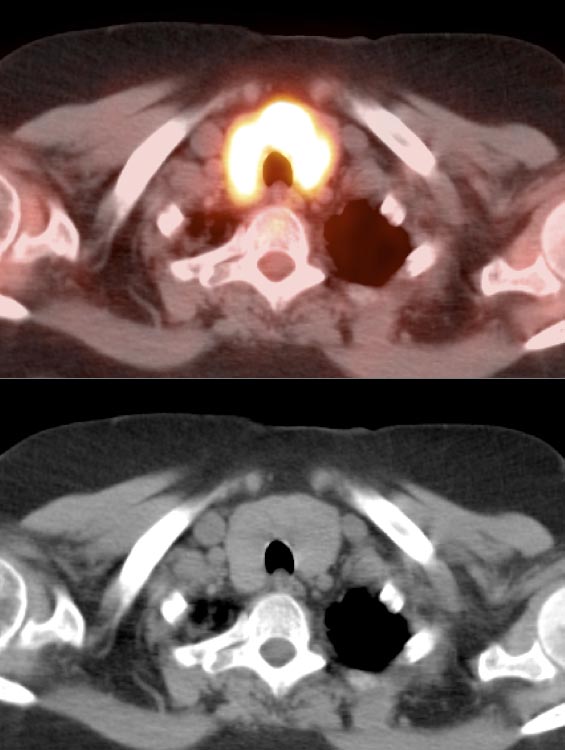

Case 4 (Image 2)

Axial images confirm the uptake to represent a hypodense left lobe thyroid nodule, containing a punctate calcification. As ≈ 30% of hypermetabolic thyroid nodules represent a primary thyroid cancer, such nodules require ultrasound evaluation (biopsy is usually necessary). In this case, biopsy revealed a primary thyroid cancer.